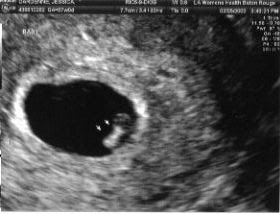

How To Read An Ultrasound At 6 Weeks

What To Expect At Your 7 Weeks Pregnancy Ultrasound Baobag